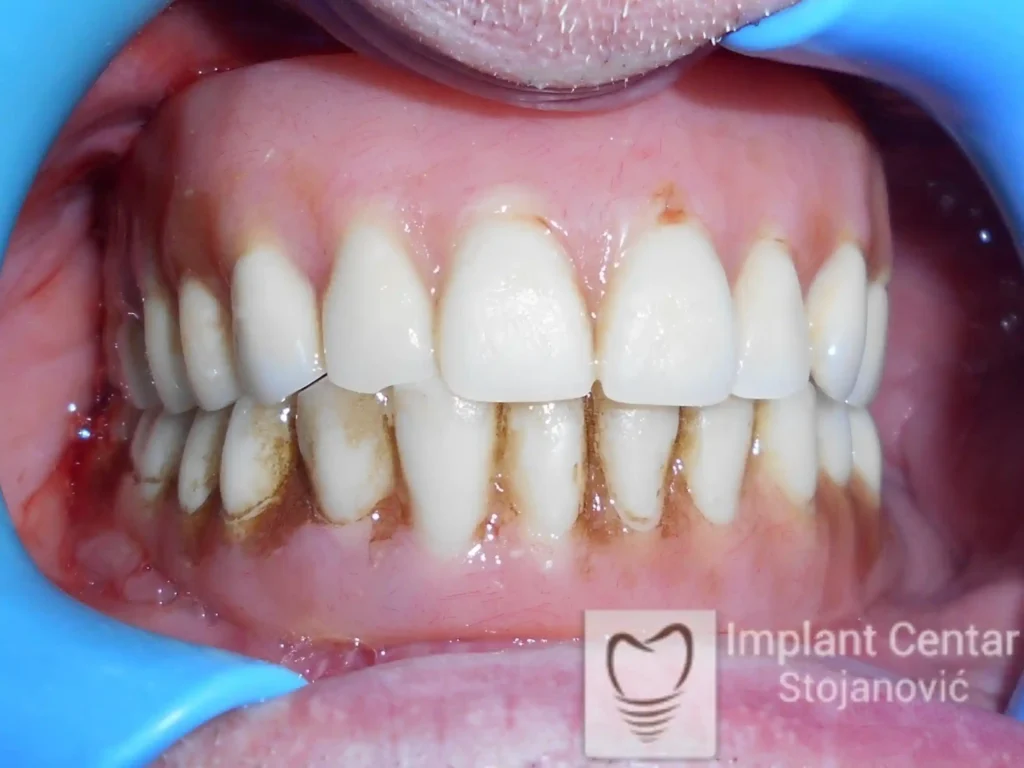

Na slikama 5. i 6. prikazan je izgled definitivnih cirkonijum-keramičkih mostova na implantatima.

Pacijent je izuzetno zadovoljan — kako estetikom novog osmeha, tako i funkcijom, jer ponovo može bez problema da jede i da se smeje.